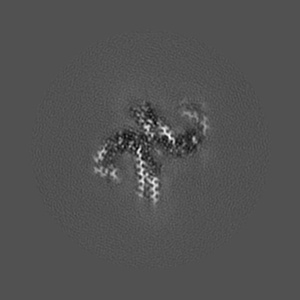

Helical reconstruction

2.68 Å

Straight filament from primary age-related tauopathy brain

Sample: Sarkosyl-insoluble fractions from primary age-related tauopathy brain

Cryo-EM structures of tau filaments from Alzheimer's disease with PET ligand APN-1607.

PUBMED: 33723967

DOI: doi:10.1007/s00401-021-02294-3